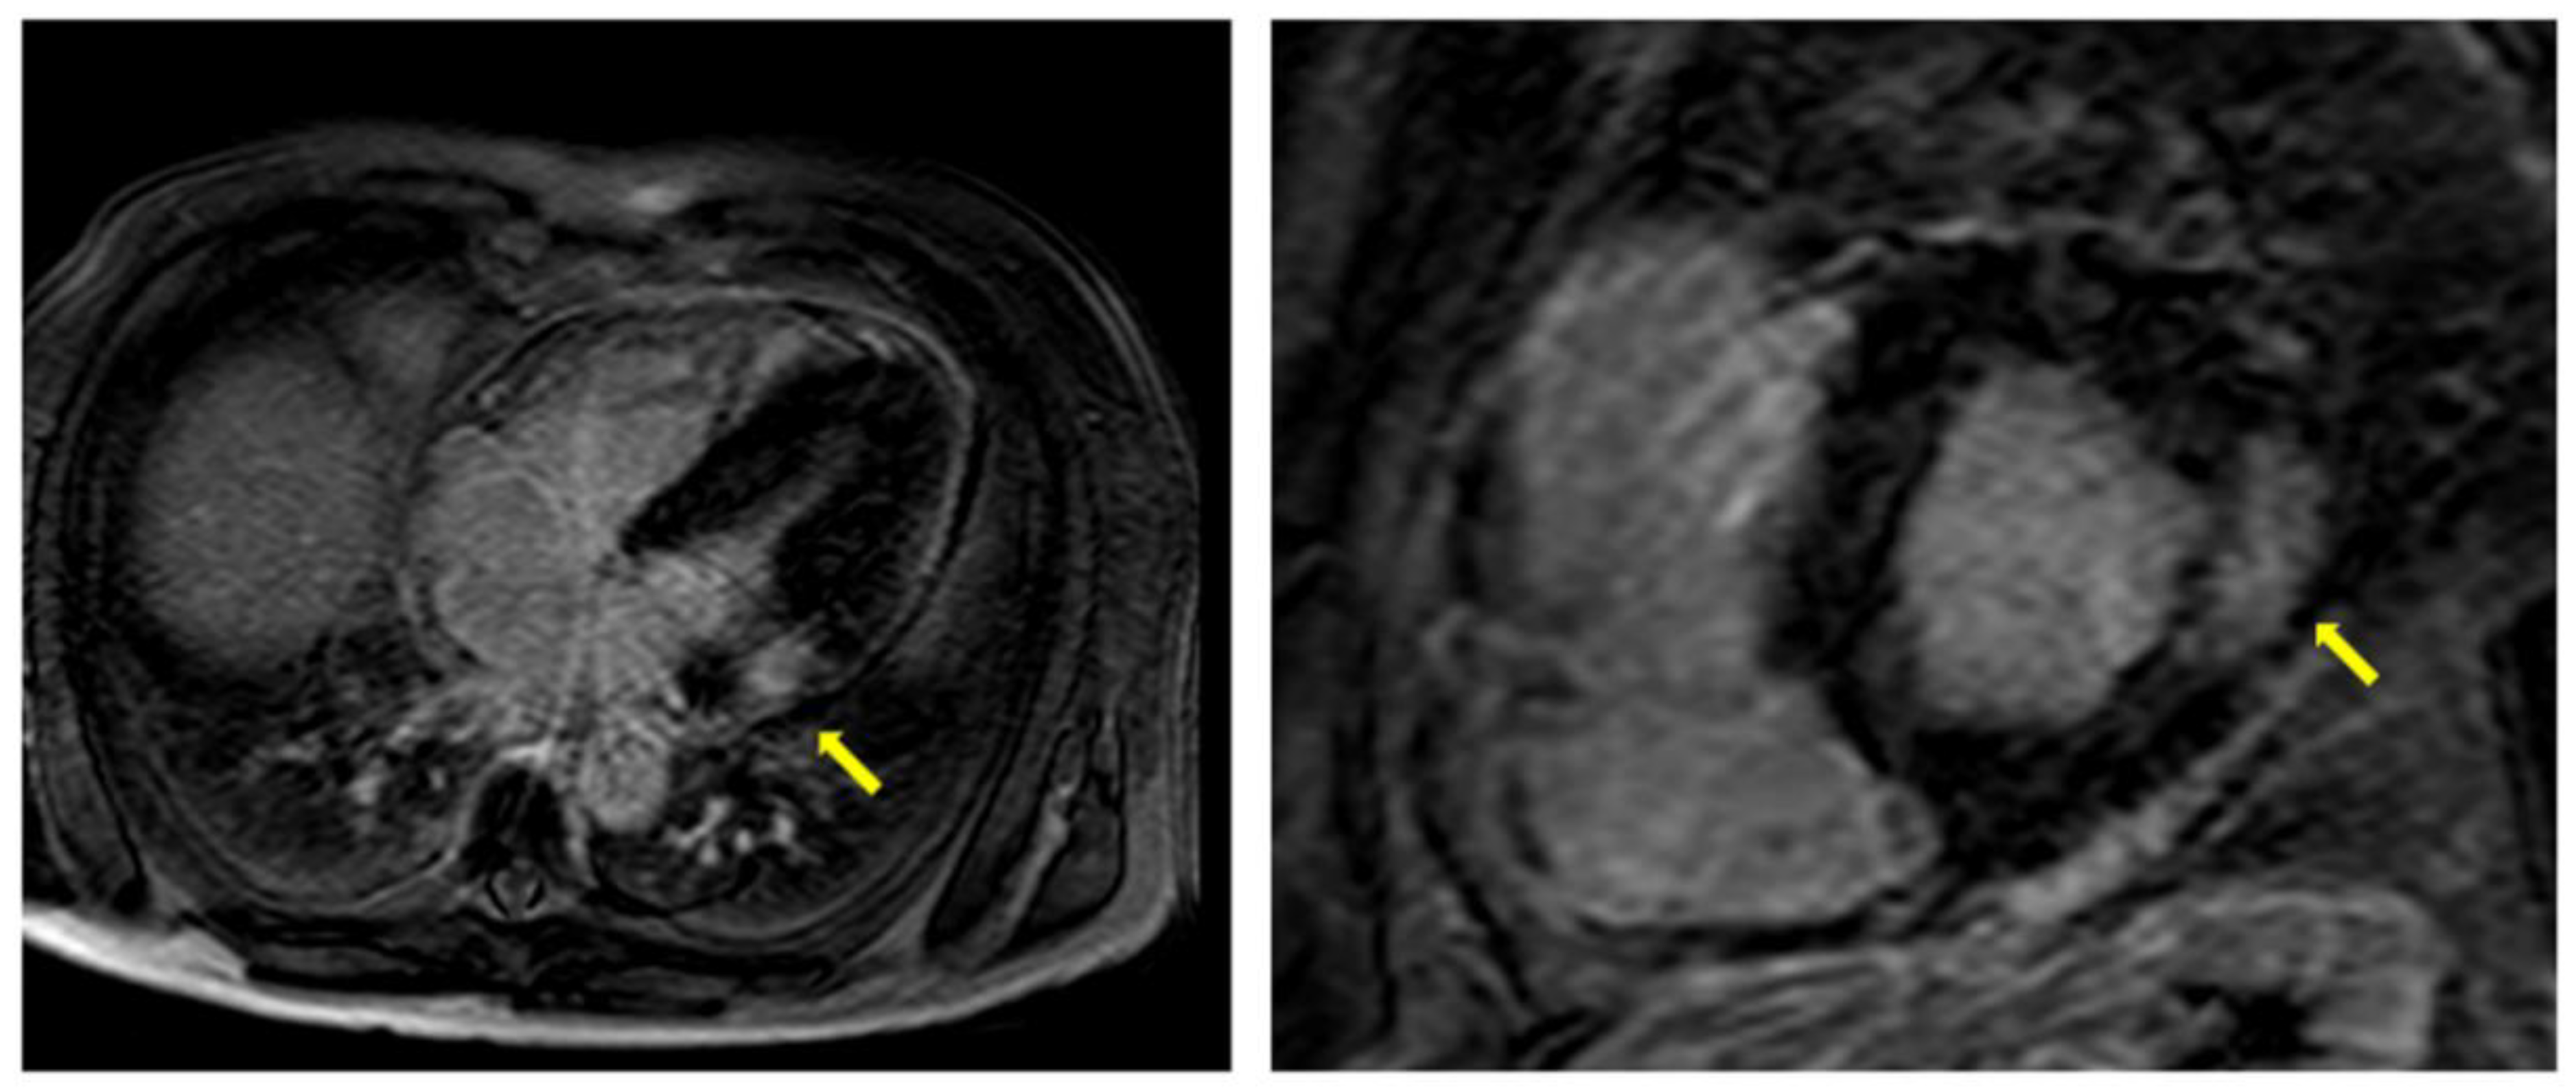

| LGE | -Fibrosis usually localized at mid-wall in the basal infero-lateral area of LV -Very extensive and diffuse in advanced AFD | -Suggestive of AFD when in the typical localization -Additionally present in patients without LVH -Strongly correlated with more CV events |

| T1 mapping | -Lower native T1 times | -Early sign of cardiac involvement -Pathognomonic of AFD -Pseudo-normalization of T1 times correlates with the presence of LGE |